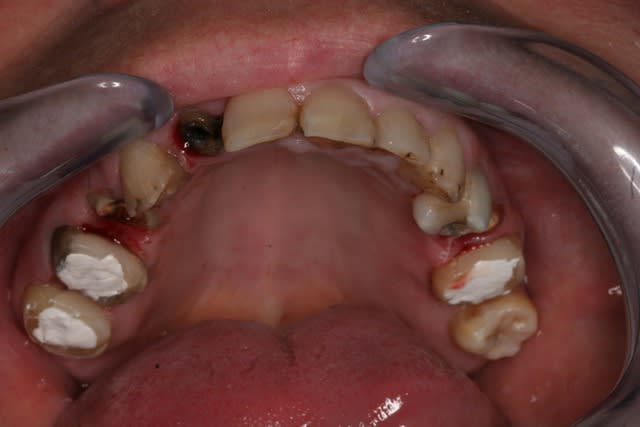

Donc la suite, évidement ortho: ingression du bloc incisivo canin sup avec ré alignement des arcades, extraction de la 14 nécessaire et ré alignement des milieux interincisif.

Pendant la finalisation du haut (axe mésio-disto incisif, à corriger à la fin pour faciliter gingivoplastie incisif sup). Il y a eu composite vestibulaire pelliculaire sous digue de 33 à 43, reprise soins et ancrage + provisoires 34,35, 36, 46; et composite sous digue 37 et 47.